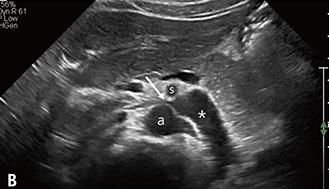

복부대동맥(a)과 상장간막동맥(b) 사이에서 왼쪽 콩팥 정맥이 눌리면서 만들어진 호두까기증후군의 초음파 영상. [논문 발췌]

호두까기증후군은 왼쪽 콩팥 정맥이 대동맥과 상장간동맥 사이에서 눌려 콩팥 안에 압력이 증가하면서 미세한 콩팥 조직과 혈관에 손상이 생기는 질환을 일컫는다.

호두까기증후군이라는 질환명은 두 동맥이 콩팥 정맥을 누르는 모양새가 마치 호두까기 기계의 집게처럼 보이고, 콩팥 정맥이 호두처럼 보인다고 해서 붙여졌다.